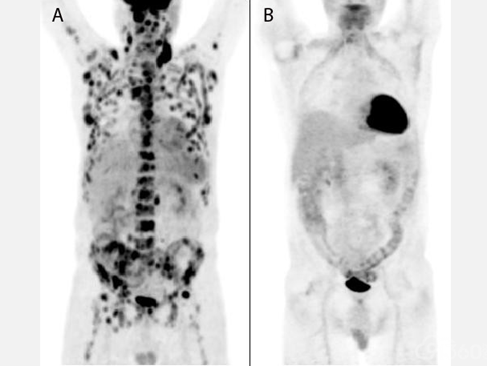

淋巴结肿大:超过2/3的经典型霍奇金淋巴瘤患者在就诊时可见淋巴结肿大,受累淋巴结通常无压痛、质地坚韧。颈部是最常见的受累部位,60%-80%的患者有颈部和/或锁骨上淋巴结肿大。

约30%的患者有腋窝淋巴结肿大,10%的患者有腹股沟淋巴结肿大。50%-60%的患者有纵隔淋巴结肿大,30%的患者有腹膜后淋巴结肿大,但体格检查无法检出。

通常先由单一淋巴结区域经淋巴管扩散至邻近淋巴结,随后累及远处或非邻近部位和器官。